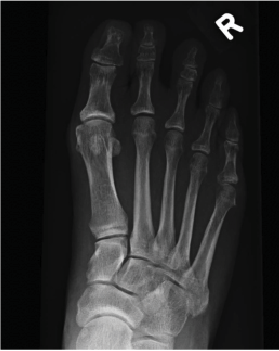

Although there are a multitude of procedures available, there are a select few that I have found to be my go-to options for pediatric flatfoot correction, and I will share them, along with relevant evaluation and examination pointers, in this article (Figure 1).

The most important imaging for pediatric flexible flatfoot deformity is a standard weight-bearing radiograph. It may be necessary to take radiographs in both normal stance and corrected foot position to see how the foot aligns. In such cases, standard angle and base of gait will show the regions of deformity and the amount of deformity while a corrected foot alignment will show hindfoot realignment and also show forefoot deformity after hindfoot realignment. For example, if there is a valgus heel position and it is realigned, a forefoot varus may be more easily visible.